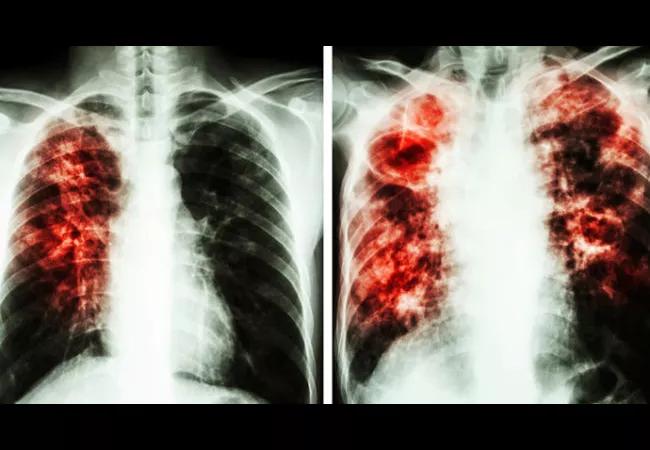

Cleveland Clinic has been named a designated Care Center of the Pulmonary Fibrosis Foundation (PFF). Cleveland Clinic’s Interstitial Lung Disease Program joins a network of more than 60 Care Centers across the U.S. specializing in the diagnosis, management and treatment of individuals with pulmonary fibrosis (PF).

Cleveland Clinic’s Interstitial Lung Disease (ILD) Program provides multidisciplinary patient- and family-centered care for patients living with conditions including pulmonary fibrosis, sarcoidosis, pulmonary alveolar proteinosis, idiopathic interstitial pneumonia, chronic beryllium disease, lymphangioleiomyomatosis and other interstitial lung problems. The program partners with patients and their families to deliver high-quality care that respects patient preferences, needs and values. Members of the team work closely with the Department of Rheumatic and Immunologic Diseases to treat connective tissue diseases. A weekly multidisciplinary conference typically focuses on cases in which the diagnosis has been challenging. After a discussion, a consensus diagnosis is reached for the majority of cases.